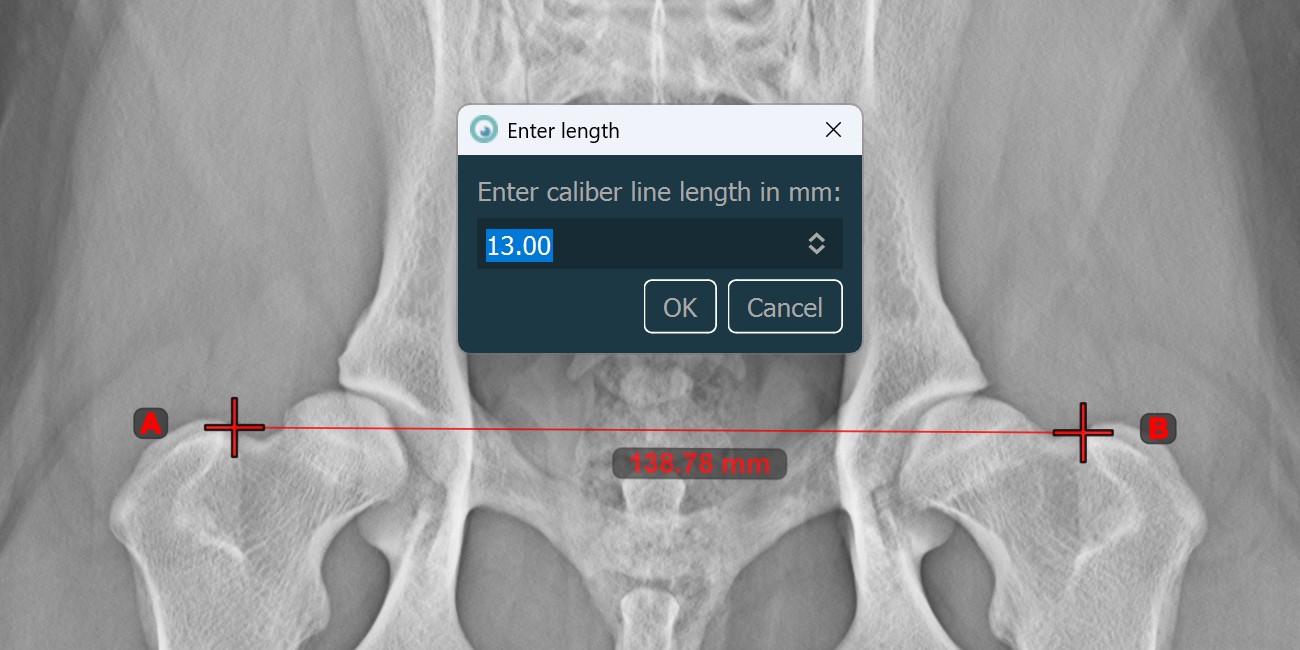

Length Calibration¶

Distances and measurement results are automatically calibrated based on pixel spacing information in the DICOM image. Use the Length Calibration tool to recalibrate the distances or set the calibration data when the information

is missing in the DICOM file.

Select the

Length Calibrationtool and assign it to one of the available mouse buttons.Measure a known distance on the image by placing the start and end points, or select them from already existing points on the image.

Specify the distance of the calibration line in millimeters and press

OKto recalibrate the image.

Information

Only one Length Calibration measurement is permitted per image. To recalibrate the image again, either unlock the calibration line and modify it, or delete it from the scene and draw it again.